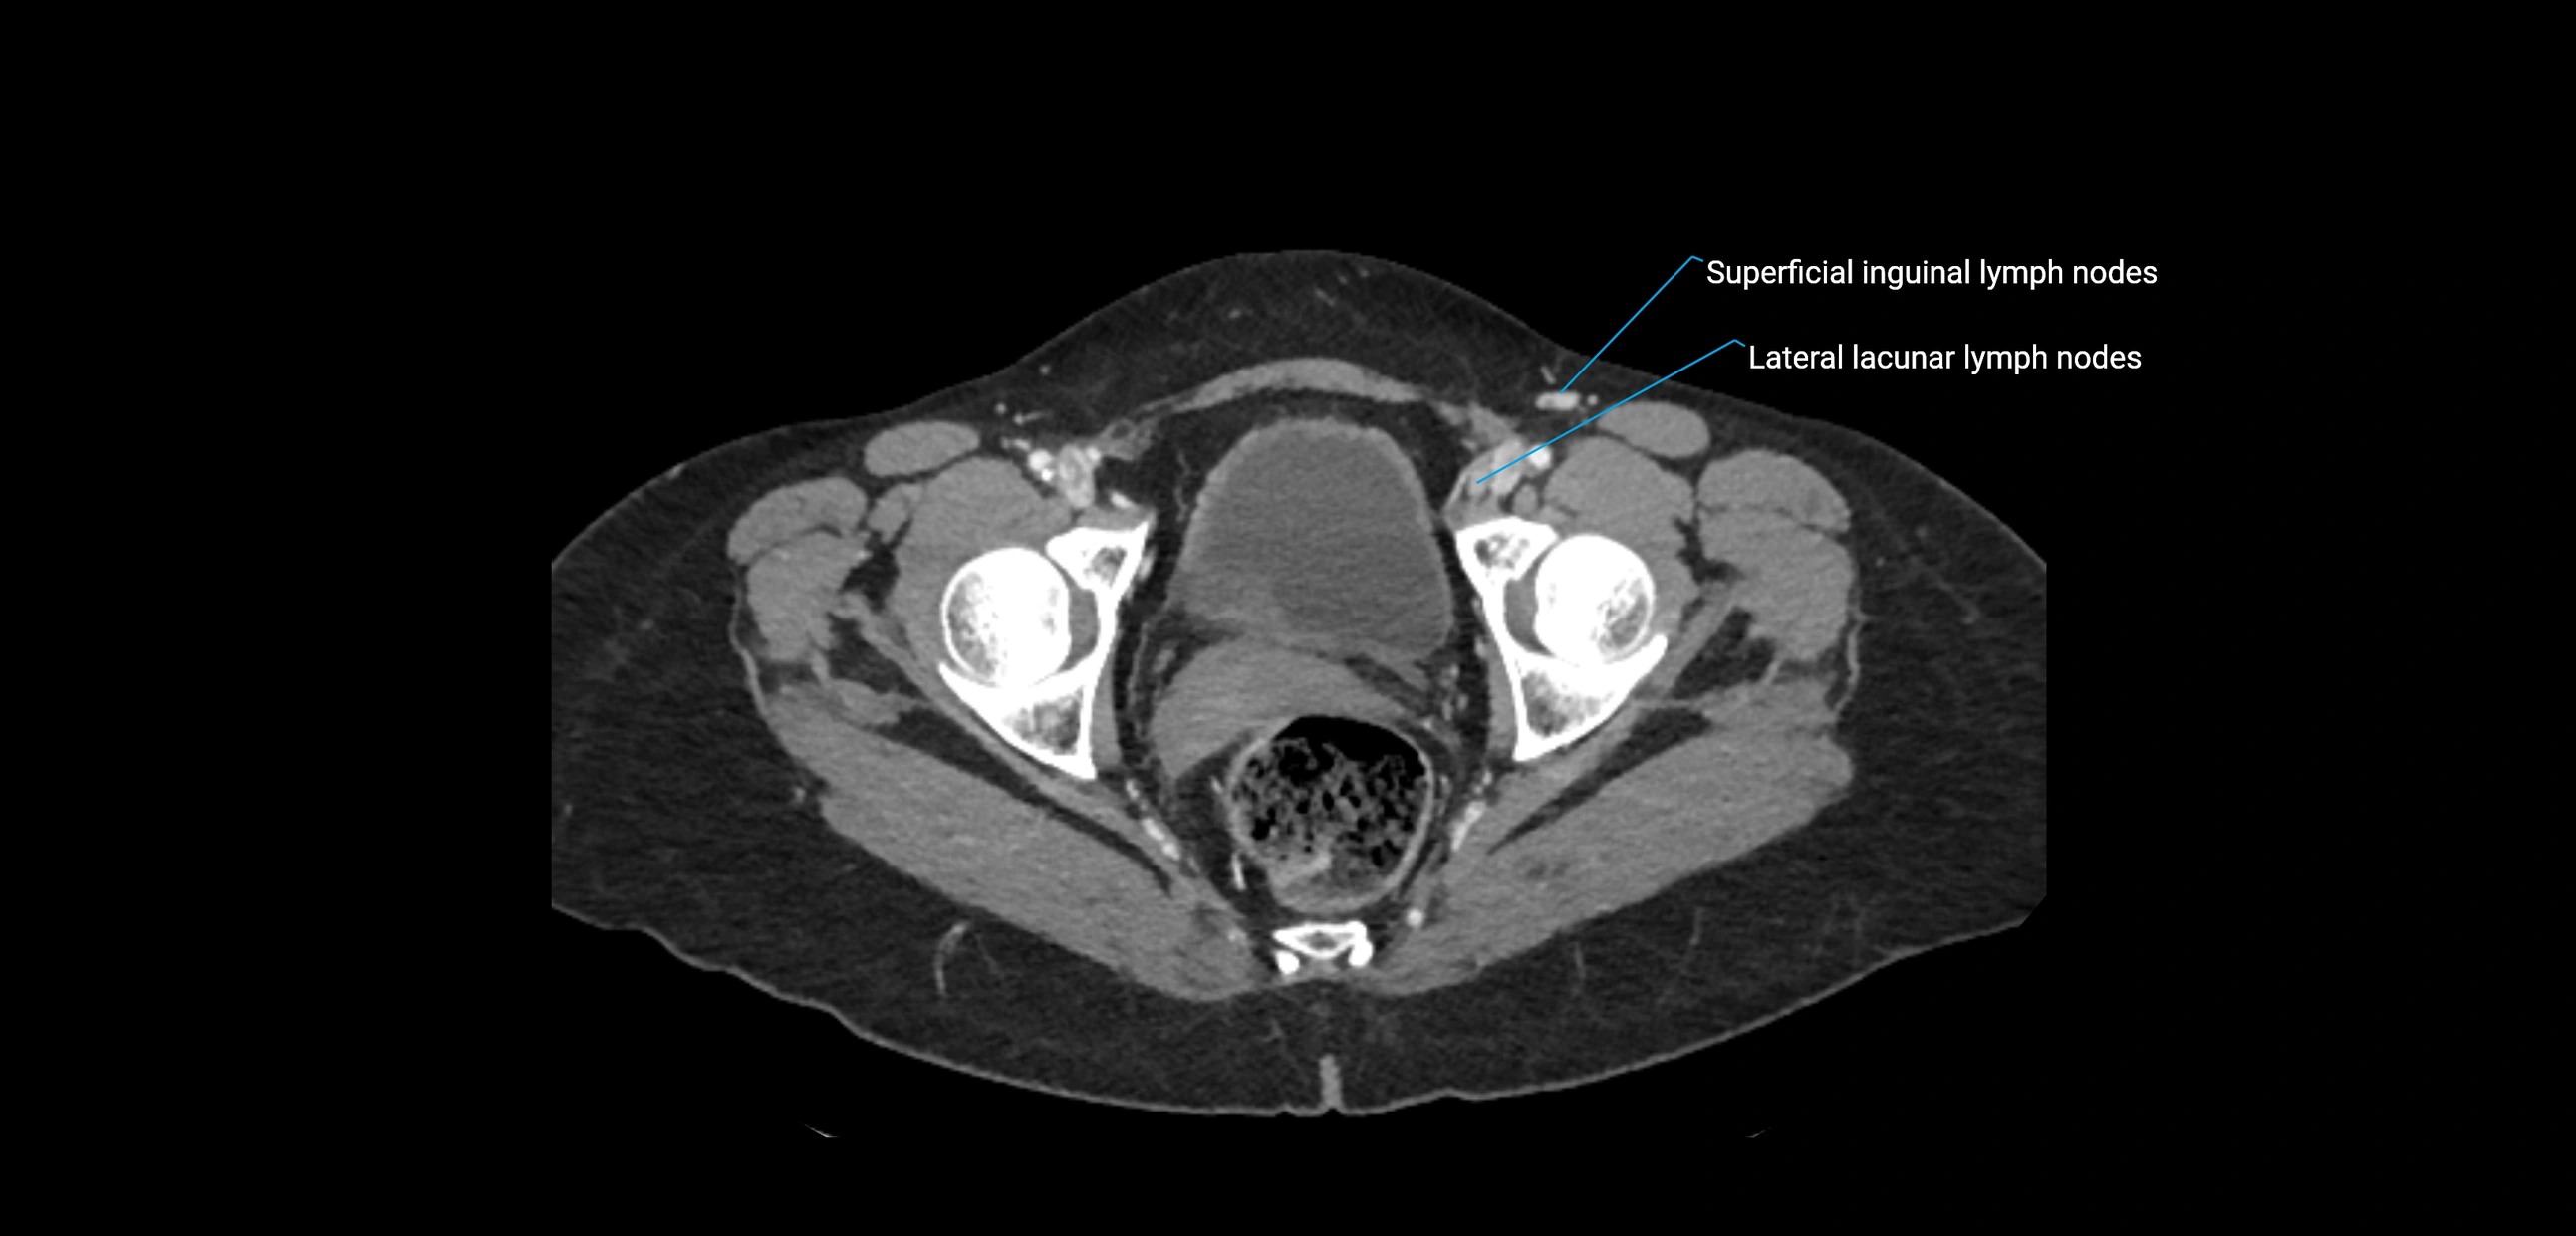

CT Appearance

CT Pre-Contrast:

• Nodes appear as soft-tissue density nodules adjacent to the aorta and IVC

• Calcification may be seen in chronic infections (e.g., tuberculosis)

CT Post-Contrast:

• Normal nodes enhance homogeneously

• Malignant nodes may show heterogeneous enhancement, central necrosis, or conglomerate formation

• Size >1 cm short axis is suspicious, though morphology and distribution are equally important